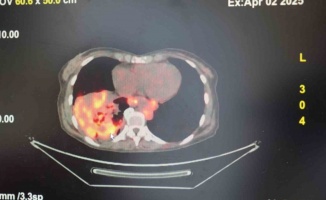

Cerrahi El Aletler ve Sağlık Müzesinde Türkiye’nin 150 yıllık tıp tarihi sergileniyor. Müzede; sedyeler, hastanelerde eskiden kullanılan hasta destek ürünleri, kadın doğum, kulak burun boğaz ve diş tedavisinde kullanılan eski cerrahi aletler gibi birçok tıbbı malzeme bulunuyor. Müzenin bir köşesinde bulunan bebek organları ise en çok dikkat çekenler arasında yer alıyor. 1980 ve 1990’lı yıllarda kimsesizlikten veya zatürre, ateşli hastalık, donarak metabolik hastalıktan dolayı henüz 6-12 aylıkken

hayatını kaybetmiş bebeklerin kalpleri ziyaretçilerin görmesi için Ondokuz Mayıs Üniversitesi Tıp Fakültesi Anatomi Anabilim Dalı Başkanlığı tarafından müzeye bağışlandı. Minik kalpler ise kimi ziyaretçileri duygulandırıyor.

Cerrahi El Aletleri ve Sağlık Müzesinin ’yaşayan müze’ formatında olduğunu belirten Doğru, "Burada resim sergileri yapılmaktadır. Okullarımız burada gösteriler sunmaktadır. Müze konserleri burada verilmektedir. Buradaki toplantı salonunda özellikle medikal firmaları, ilaç firmaları ve farklı sektörden işletmeler aylık, haftalık toplantıları yapmaktadır. Müzemiz hem sağlık bilimleri fakültesi öğrencilerinin hem tıp fakültesi öğrencilerinin uğrak yeridir. Öğrencilerimiz burada ders çalışma imkanı buluyorlar ve sosyalleşiyorlar. Öte yandan Samsun’da Tıbbi Cihazlar Anadolu Meslek Lisemiz var. Sektörümüze elaman yetiştiriyor. Biyomedikal teknikerliği, biyomedikal mühendisliği bölümümüz var. Buralarda okuyan öğrencilerimiz de müzemizi sık sık ziyaret ederek buradan istifade ediyorlar. Müzemiz, sağlık bilimleri ve tıp fakültesi öğrencilerinin ilgisini çekiyor. Buradaki eserler ve organlar öğrencilerin inceleme ve araştırma yapmalarına da imkan sağlıyor" diye konuştu.